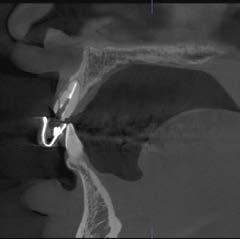

Der Patient berichtete anamnestisch über ein Trauma im linken vorderen Oberkiefer. Mit dem 3D R100 wurde ein DVT des Oberkiefers erstellt. Sowohl die sagittale, als auch die vertikale Ansicht zeigten eine horizontale Fraktur im bukkalen Bereich des Zahnhalses des endodontisch behandelten linken seitlichen Schneidezahnes. In der Sagittalebene stellte sich auch eine Perforation der bukkalen Knochenlamelle dar.